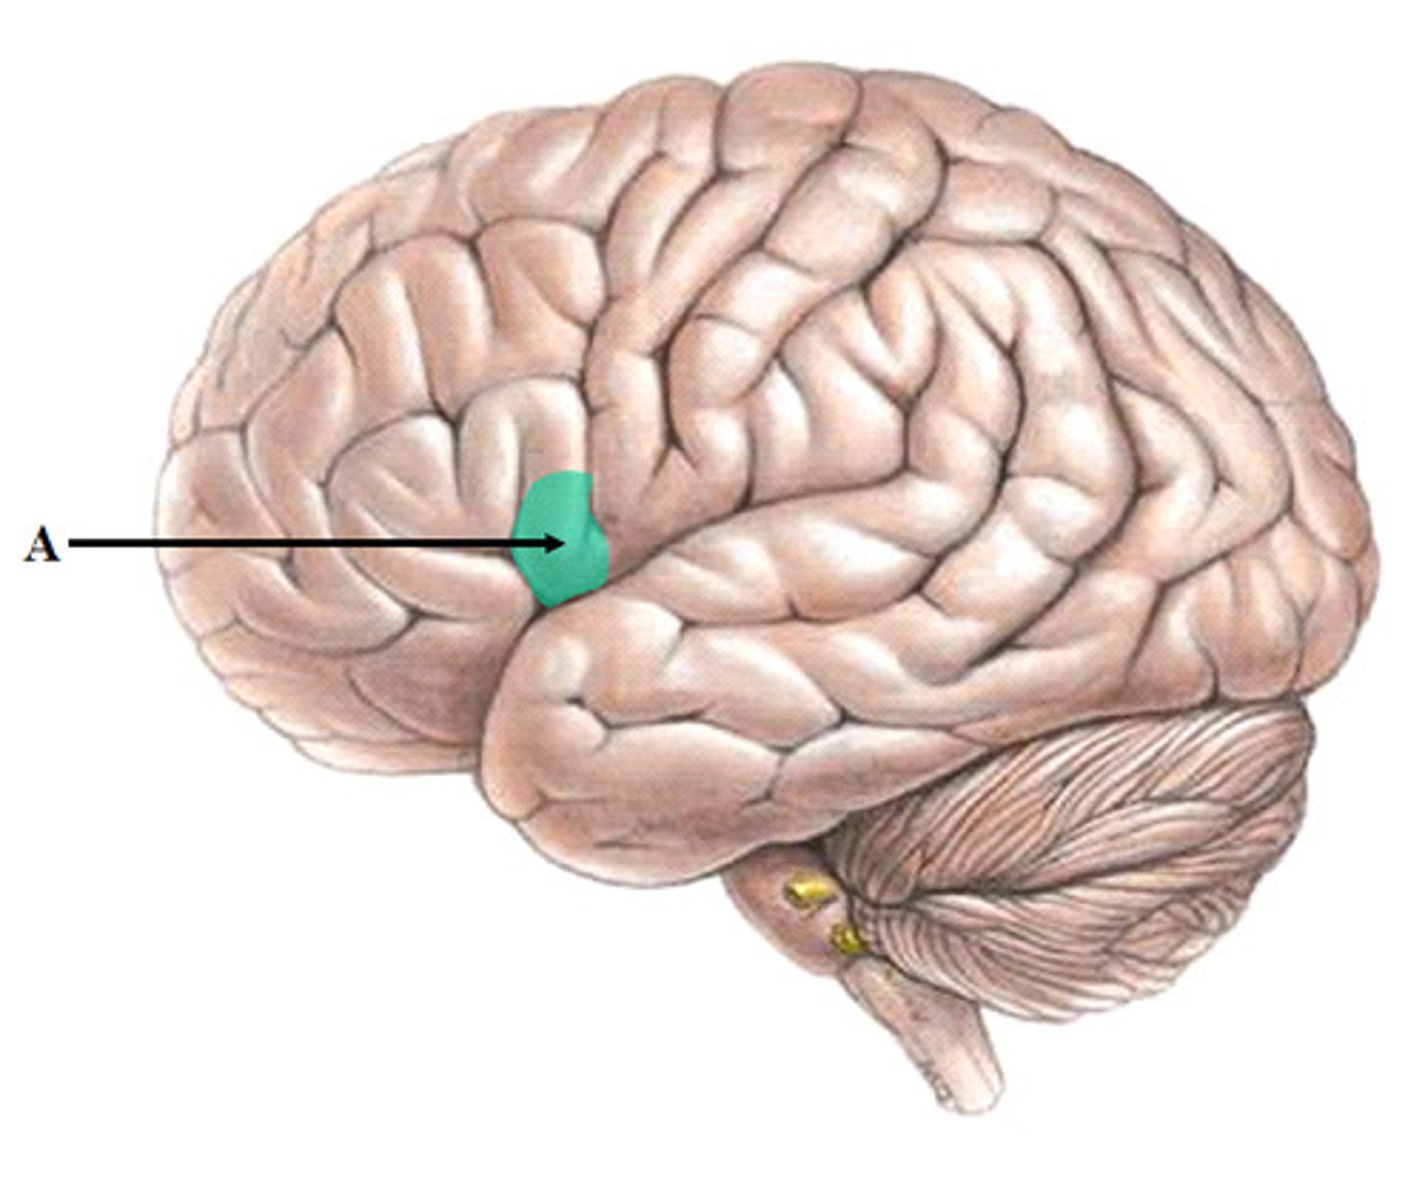

Broca's area

language center located in the left frontal lobe

involved in expressive language

if damaged, you are not able to speak

boca in Spanish means mouth